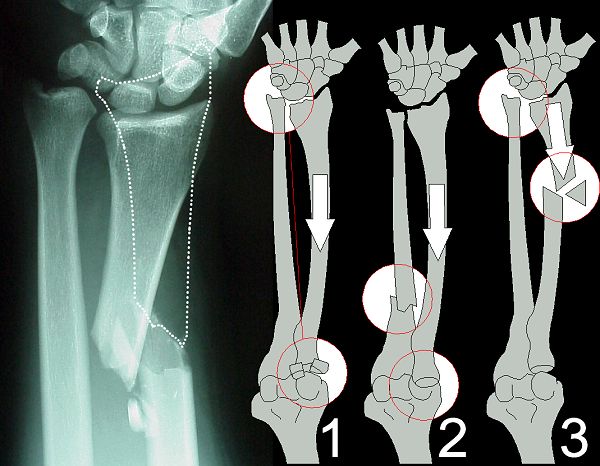

Figure Legend: Combined fractures include

three special combinations of injury: the Essex-Lopresti lesion (1),

Monteggia fracture-dislocation (2), and Galeazzi fracture-dislocation (left

and 3). Galeazzi fracture-dislocation refers to a fracture of the shaft

of the radius associated with dislocation of the distal radioulnar joint.

Monteggia fracture-dislocation refers to fracture of the ulna with dislocation

of the radial head. Each of these fracture-dislocation patterns is best

treated with open fracture reduction and closed treatment of the dislocation.

Essex-Lopresti lesion refers to longitudinal disruption of the radioulnar

interosseous membrane and proximal migration of the radius associated with

fractures involving the proximal radioulnar joint, the distal radioulnar

joint, or both sites. The most common presentation of Essex-Lopresti is

associated with radial head excision for fracture, resulting in ulnocarpal

impingement syndrome. Treatment is controversial. When diagnosed acutely

in the context of an unreconstructable radial head fracture, Essex-Lopresti

justifies use of a temporary radial head implant. Late surgical options

include ulnar shortening osteotomy or the developing technique of ligament

reconstruction with a tendon graft.